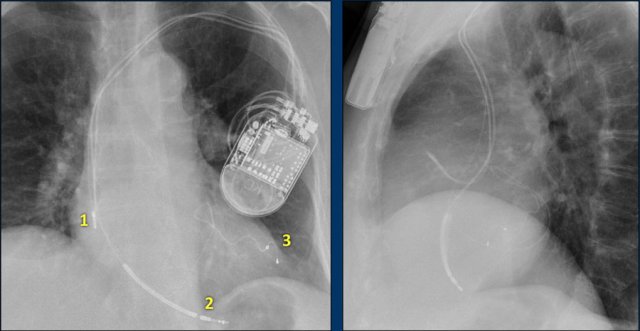

The findings are:

• Two epicardial leads connected to pacemaker

• ICD

• two leads to right ventricular apex

• one lead contains two shock coils

• tricuspid valve (arrows)

• mitral valve